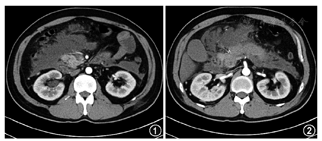

患者 男性,37岁,因"上腹部疼痛2 d"于2013年8月31日入院。患者就诊前2天突发上腹部胀痛,阵发性加重,伴有恶心、呕吐,呕吐物为胃内容物。当地医院腹部CT检查结果提示急性胰腺炎(acute pancreatitis,AP),给予抗炎、补液等对症支持治疗后疼痛无明显好转,且伴有全身肌肉酸痛乏力,遂转入我院胰腺中心治疗。病程中患者未饮食,大小便自解,自诉尿液为棕色,伴低热。入院体检:体温38.1 ℃,脉搏120次/min,呼吸频率24次/min,血压152/90 mmHg(1 mmHg=0.133 kPa),腹平软,全腹部明显压痛,反跳痛、肌紧张不明显,未及肿块,肝脾肋下未及,Murphy征阴性,移动性浊音阴性,肠鸣音正常。入院后辅助检查:动脉血气pH值为7.371,PaO2为162 mmHg(鼻导管吸氧5 L/min),PaCO2为162 mmHg,碱剩余为6 mmol/L;血清淀粉酶121 U/L(正常值:0~110 U/L),血清脂肪酶241.1 U/L(正常值:0~60 U/L);生化检查:尿素氮7.03 mmol/L,肌酐99.3 μmol/L,ALT 42.7 U/L,AST 63.6 U/L,肌酸激酶(creatine kinase,CK)7 337 U/L(正常值:25~190 U/L),乳酸脱氢酶2 150 U/L(正常值:313~618 U/L),甘油三酯9.65 mmol/L,血糖18.0 mmol/L,血钙2.07 mmol/L;肌红蛋白>1 000 μg/L(正常值:0~46 μg/L);血常规:白细胞计数7.78×109/L,中性粒细胞百分比86%,血红蛋白浓度156 g/L;尿常规:尿糖(+++),尿酮体(-),尿蛋白(-);糖化血红蛋白9.3%。腹部增强CT检查:胰腺肿胀,胰周大片渗出,符合AP表现(图1,图2)。